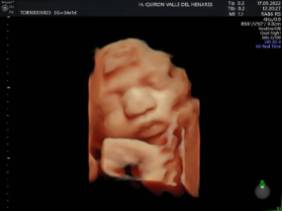

El Hospital Quirónsalud Valle del Henares incorpora un nuevo ecógrafo con tecnología 5 D

El Hospital Quirónsalud Valle del Henares ofrece la posibilidad de realizar ecografías gestacionales 5D. Este tipo de exploración permite obtener una imagen muy realista del bebé y se puede realizar en cualquier etapa de la gestación -aunque lo recomendado es realizarla entre las semanas 28 y 32 de gestación, ya que técnicamente es el mejor momento y es mucho más probable obtener imágenes de buena calidad-.

Al final de la prueba, se entrega a la familia un informe de la ecografía y un soporte digital que contiene las imágenes y los vídeos realizados. Las ecografías 4D y 5D son también llamadas emocionales por la explosión de sensaciones que genera cuando la madre ve por primera vez la imagen del bebé que espera.

"Realizar esta ecografía con nuestro equipo de diagnóstico prenatal tiene un valor añadido -señala la Dra. Rocío Vellido Cotelo, Jefa Asociada de Ginecología y Obstetricia del Hospital Quirónsalud Valle del Henares, dado que quien realiza la prueba es un especialista en la materia, siempre se completa la exploración con un examen morfológico y de perfil biofísico fetal, que permita valorar el estado de bienestar del bebé más allá de la captura de videos y fotografías".